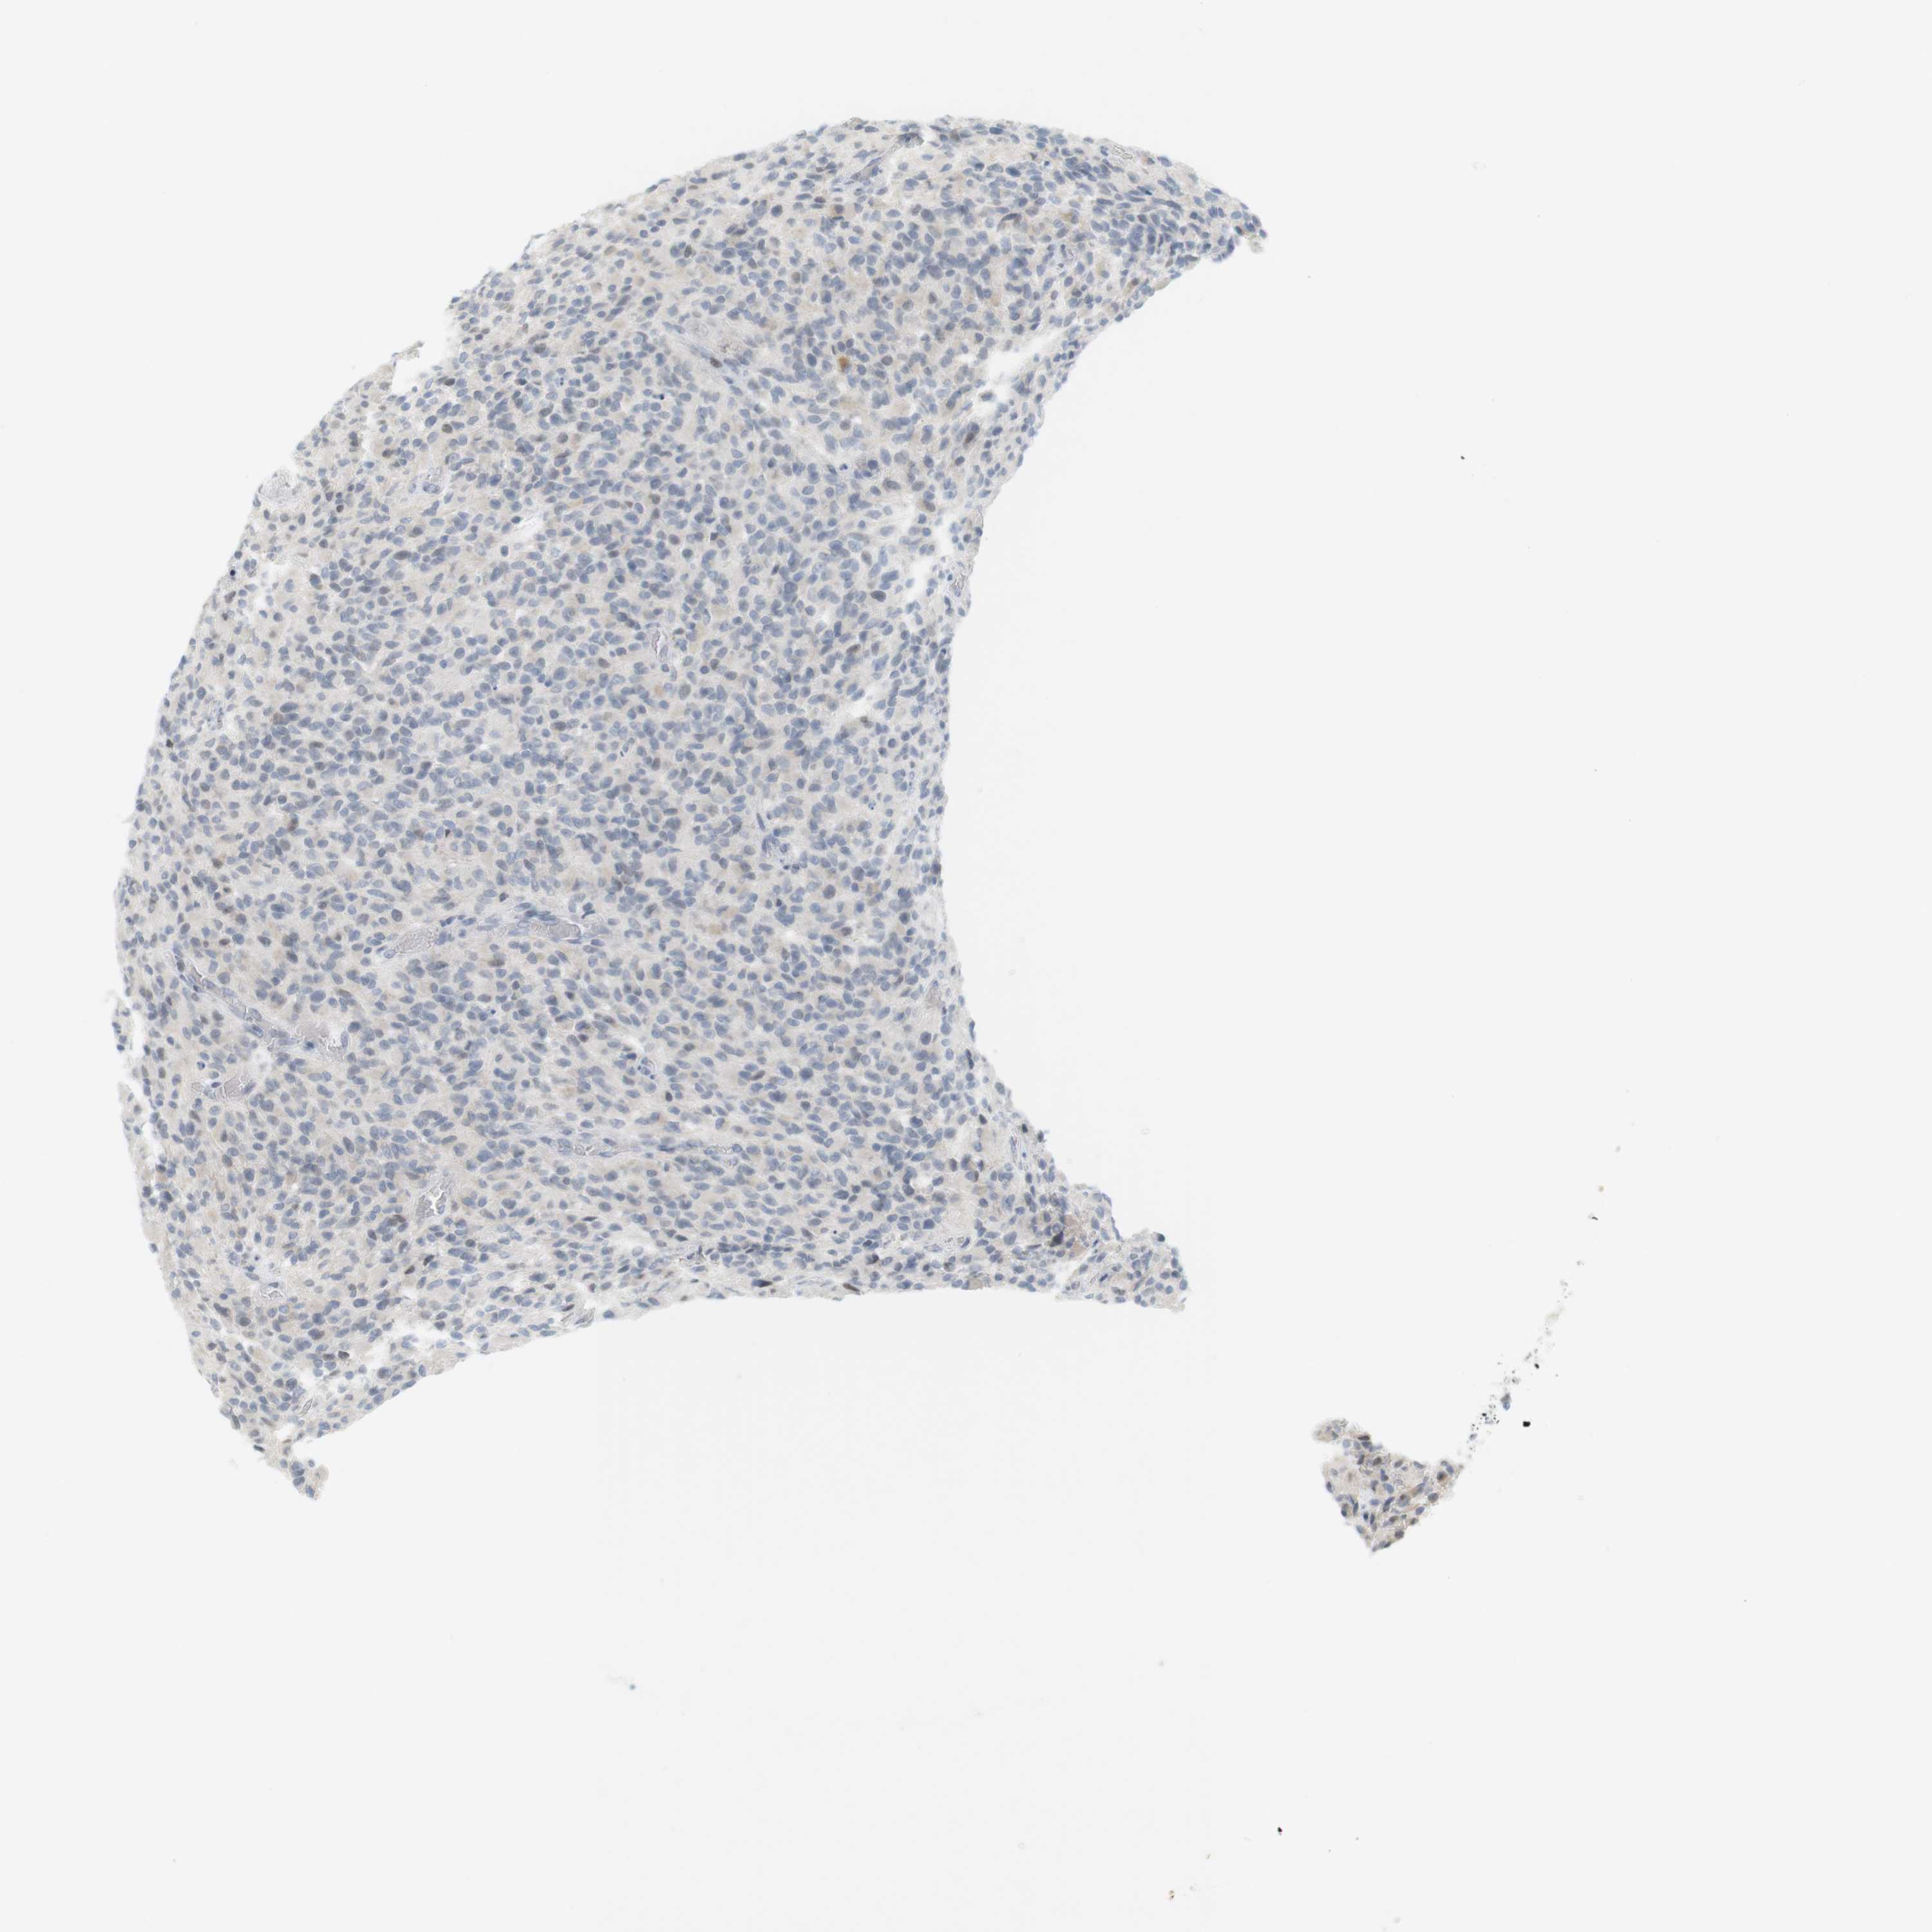

GLIOMA - Protein expressioni

A mouse-over function shows sample information and annotation data. Click on an image to view it in a full screen mode. Samples can be filtered based on level of antibody staining by selecting one or several of the following categories: high, medium, low and not detected. The assay and annotation is described here.

Note that samples used for immunohistochemistry by the Human Protein Atlas do not correspond to samples in the TCGA dataset.

Antibody stainingi

Antibody staining in the annotated cell types in the current human tissue is reported as not detected, low, medium, or high, based on conventional immunohistochemistry profiling in selected tissues. This score is based on the combination of the staining intensity and fraction of stained cells.

Each image is clickable and will lead to virtual microscopy that enables deeper exploration of all samples and also displays staining intensity scores, fraction scores and subcellular localization as well as patient and tissue information for each sample.

Antibody HPA001232

Antibody CAB015397

Staining

High

Medium

Low

Not detected

Intensity

Strong

Moderate

Weak

Negative

Quantity

>75%

75%-25%

<25%

None

Location

Nuclear

Cytoplasmic/membranous

Cytoplasmic/membranous,nuclear

Glioma, malignant, High grade

Glioma, malignant, Low grade